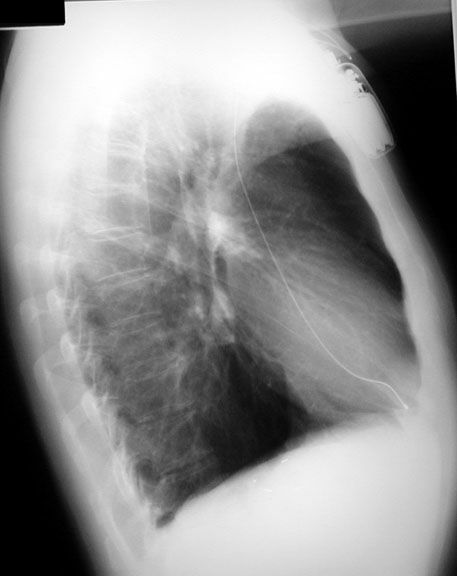

Pacemaker:  Note the path of the catheter from the right side.